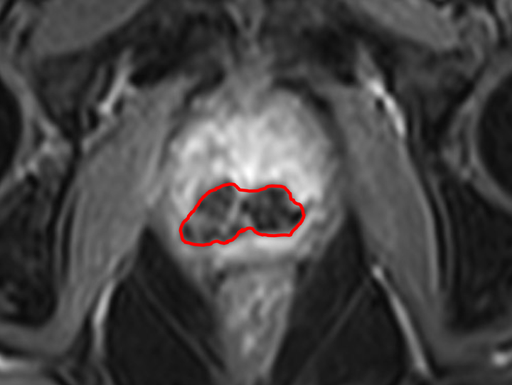

MR images

Image 2 shows the effect of the treatment of patient 10. Treatment for patient 10 was focal, meaning that the purpose was only to treat the part where the tumour was present and not the entire prostate gland. In the image this is shown as the dark area in the lower part of the prostate. The light part of the prostate, in the upper part of the image, indicates untreated tissue.